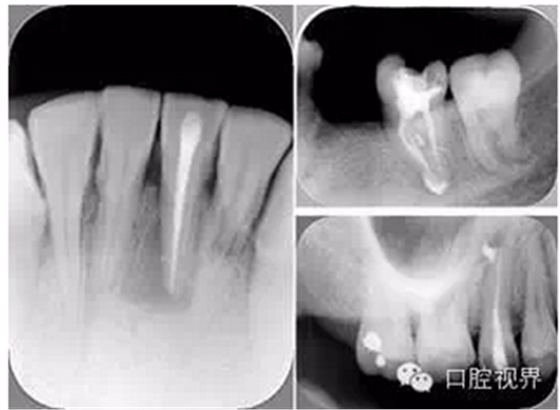

( 2 )髓腔其他改變:如髓室頂、繼發(fā)性牙本質、修復性或增齡性牙本質。見左圖。

右圖中有繼發(fā)性牙本質,切削后獲得直線通路。

( 1 )術前:術前 X 線片用來了解牙齒的大概情況。術前預期為多根牙時 X 線片應偏頭拍攝。

( 2 )診斷絲:根據(jù)術前 X 線片進行開髓、根管的初步預備后,需要插入診斷絲,用來指示工作器械位置。常用 10 號或 15 號擴大器作為診斷絲插入牙髓腔。

( 3 )主牙膠尖確認:通過術前預期和診斷絲診斷,明確工作長度、牙根走向,進行根管預備。之后應進行主牙膠尖(中銼)確認,已明確根管是否適合充填。

( 4 )術后:觀察治療效果。